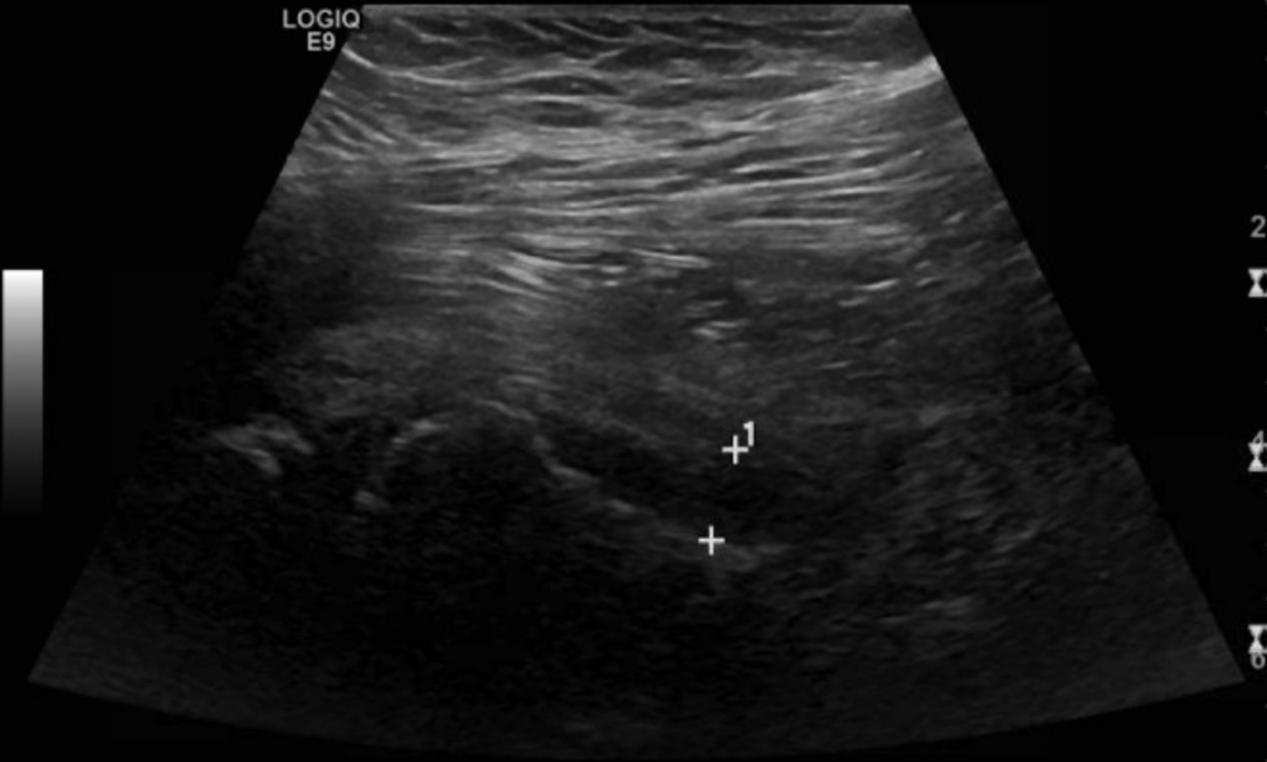

骨盆和右侧髋关节的x线片显示右侧SCFE,骺骨干角度(Southwick角)为75°(图1)。超声检查显示右侧髋关节积液(图2)。这些图像和检查证实患者目前诊断为急性严重不稳定的SCFE。病人在手术室进行了前Smith-Peterson入路,并进行了囊膜切开术,显示出有关节出血的情况。在干骺端前部轻轻按压复位。在干骺端放置两个空心螺钉以保持复位。对侧髋关节也被预防性固定非典型SCFE(图3)。

图2